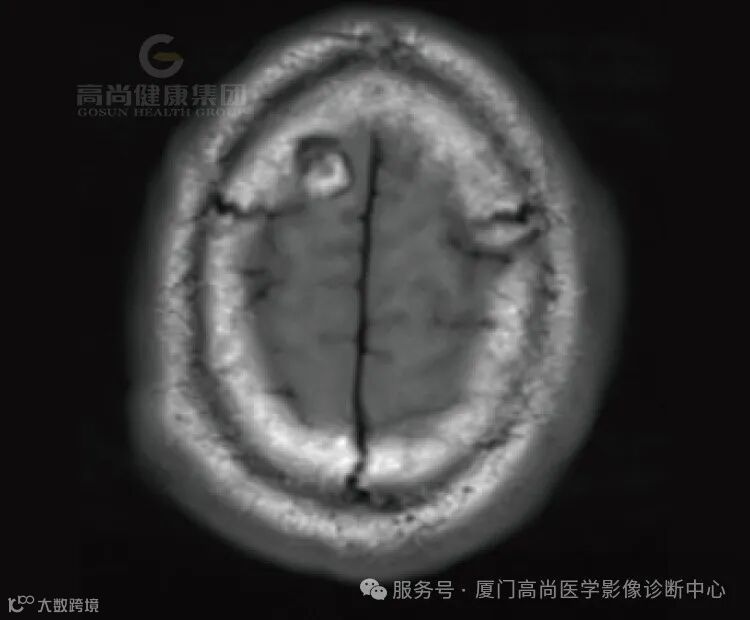

患者代诉左侧肢体无力半月余,既往高血压史。

1.右侧丘脑、基底节、放射冠区病灶,考虑脑出血(亚急性期)并破入右侧脑室,中线结构局部左偏,请结合临床。

2.右侧额叶团状稍高异常信号影,相邻右侧额骨局部孔状影,请结合临床,建议复查。

3.脑白质病变(Fazekas评分,3分)。